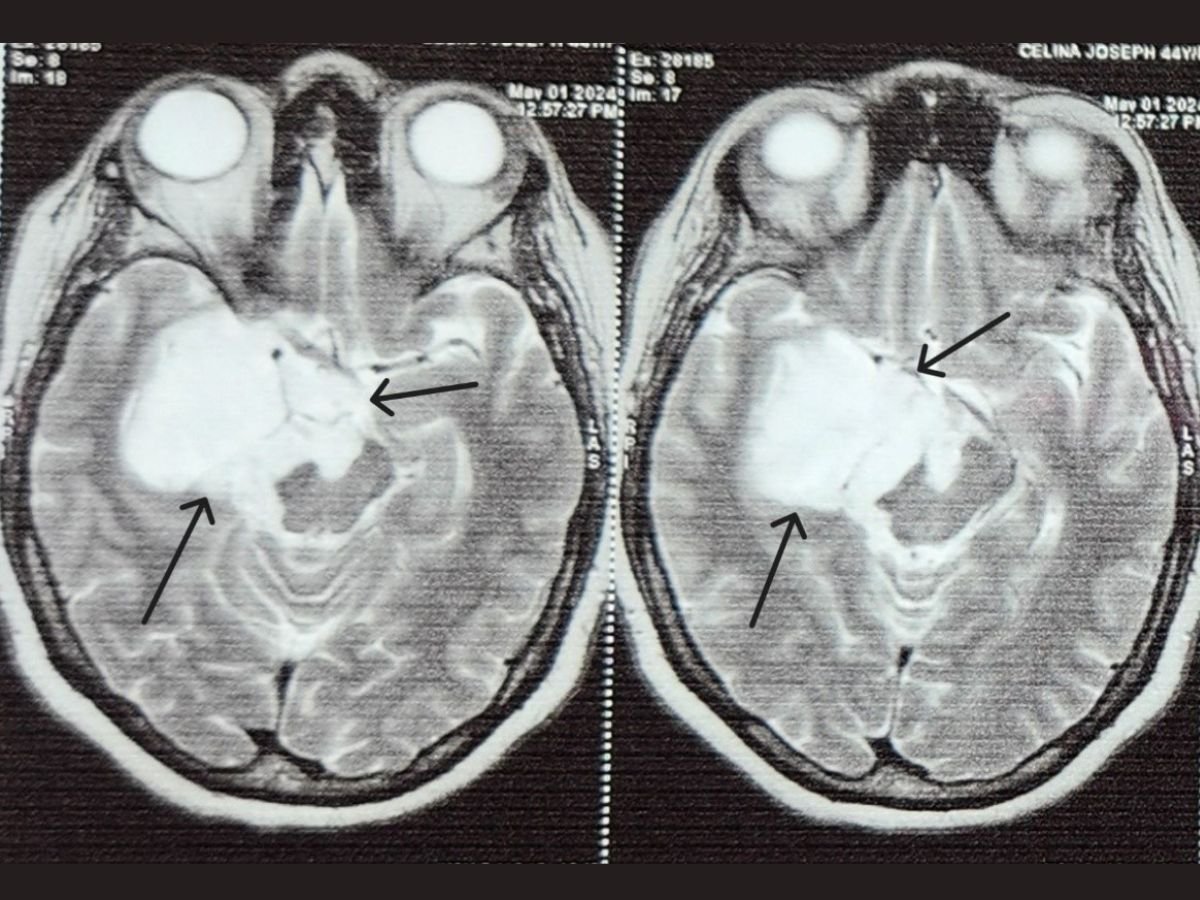

After an epidermoid tumor was found underneath a 45-year-old dessert chef’s brain through Magnetic resonance imaging who had recurrent seizures sought assistance from Dr. L H Hiranandani Hospital. The tumor had enveloped important nerves that help in vision and eye movement causing serious impairment of her sight and increasing the number of seizures.

Epidermoid tumors are non- cancerous, usually slow-growing masses occurring as a result of errors in cell migration during embryonic stage of development. These tumours contain a thick yellow substance called keratin and may compress neighboring areas of the brain leading to severe neurological symptoms.